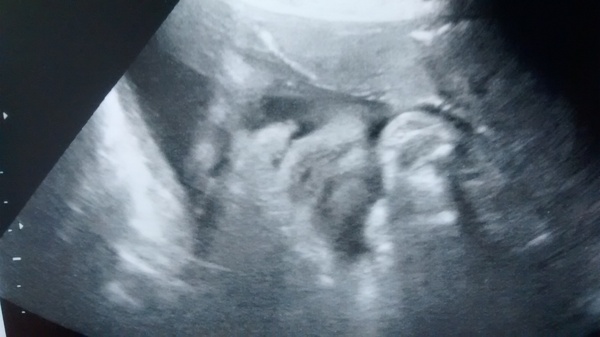

Had my scan this avo and all is well, due to being 38 weeks baby is a squished wee lump in there so I couldn't have seen whether it was pink or blue if I wanted to, got a funny pic tho of a pouty frowning face! Baby measuring 50th centile, they didn't estimate a weight, said there's no point as they can be so inaccurate, but looks to be a nice healthy wee squish anyway Grin